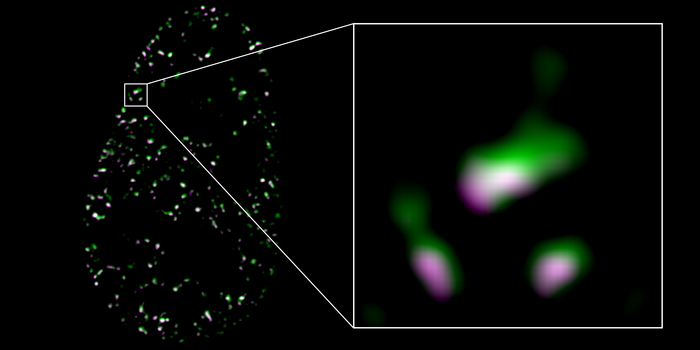

暴露在性激素二氢睾酮下的细胞的超高分辨率显微图像。细胞核中可见雄激素受体(紫色)和肌动蛋白(绿色)。两种分子都用荧光染料染色,因此可见。单个结构(右)只有200纳米(一毫米的2百万分之一)小。

图源:Julian Knerr / Freiburg大学

研究人员使用高分辨率3D SIM显微镜来检查DAAM2是否对性激素的影响确实很重要。这是一项精细的技术,可用于观察细胞内的分子运动。图像显示DAAM2和肌动蛋白直接在细胞核内与雄激素受体共定位。进一步的实验表明,这种共定位对基因活性的控制是重要的。